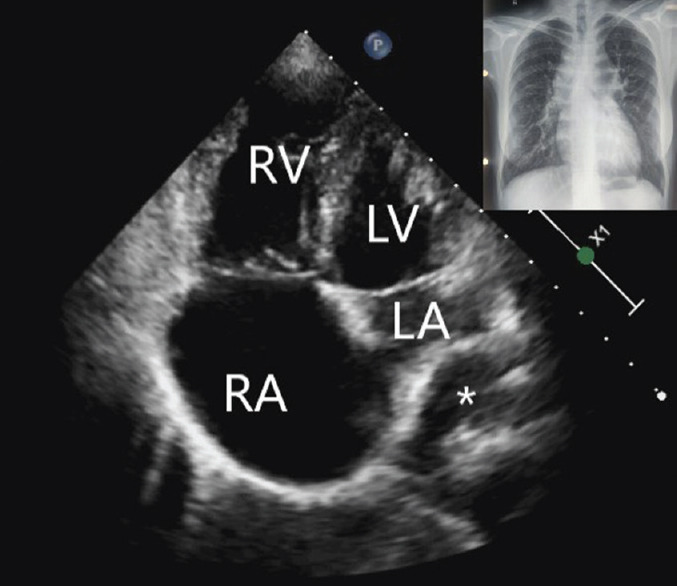

全肺静脉连接异常(TAPVC)是一种罕见的紫绀型先天性心脏病,成年后存活的患者更是少之又少。在此,我们介绍了一例 26 岁女性的病例,她在怀孕期间偶然被诊断出患有心上型 TAPVC。所有四条肺静脉汇合成一条共同的静脉汇流口,排入一条左侧垂直静脉,该静脉排入腹股沟静脉。

Total anomalous pulmonary venous connection (TAPVC) is a rare cyanotic congenital heart disease and their survival into adulthood is even rarer. Here, we present the case of a 26-year-old female who was incidentally diagnosed with a case of supracardiac TAPVC during her pregnancy. All four pulmonary veins were joining to form a common venous confluence which drained into a left-sided vertical vein which drained into the innominate vein.